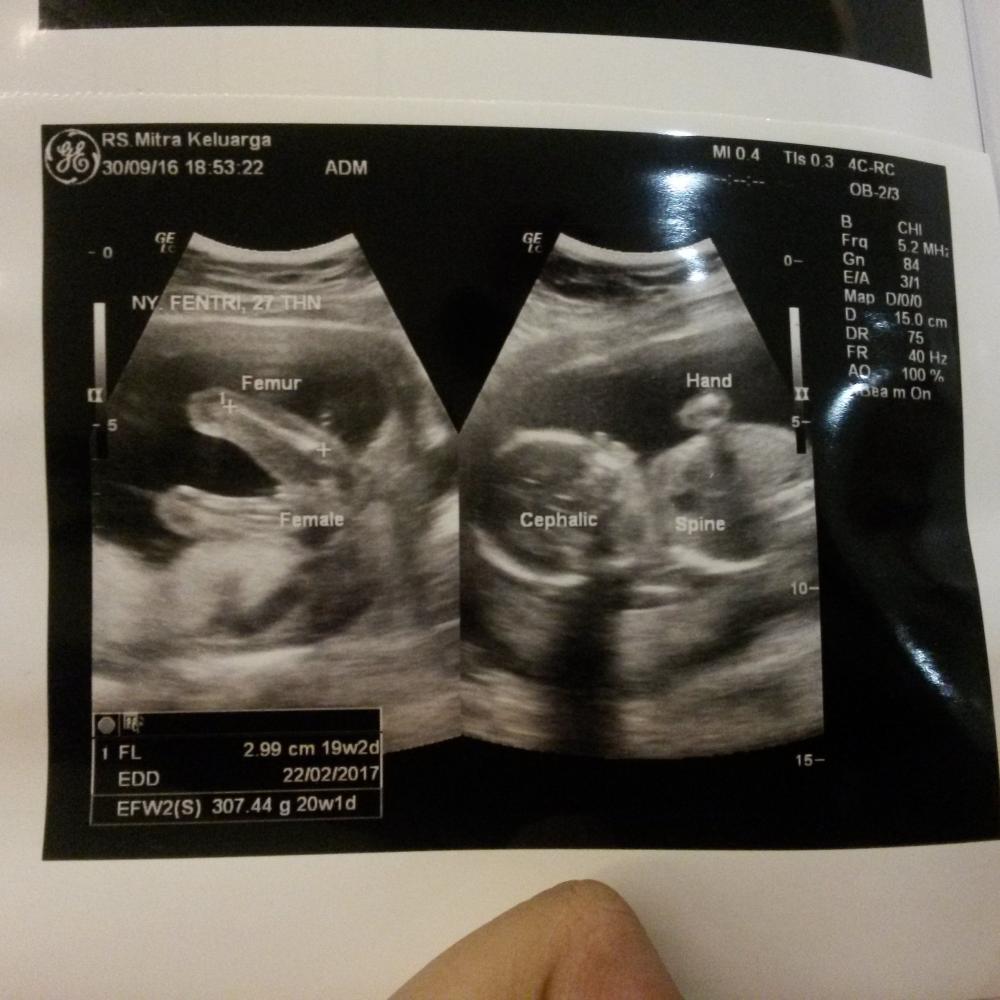

Foto Usg 2 Dimensi Uk 21 Weeks Ibuhamil Com

Foto Usg 2 Dimensi Uk 21 Weeks Ibuhamil Com

Usg 4 Dimensi Penjelasan Hasil Usg Trimester 2 Dan 3 Seperti Pada Postingan Saya Sebelumnya Hasil Usg Dalam Bentuk Gambar Yang Di Print Ada Beberapa Keterangan Di Dalamnya Keterangan Pada Gambar

Usg 4 Dimensi Penjelasan Hasil Usg Trimester 2 Dan 3 Seperti Pada Postingan Saya Sebelumnya Hasil Usg Dalam Bentuk Gambar Yang Di Print Ada Beberapa Keterangan Di Dalamnya Keterangan Pada Gambar

Usg 4 Dimensi Penjelasan Hasil Usg Trimester 2 Dan 3 Seperti Pada Postingan Saya Sebelumnya Hasil Usg Dalam Bentuk Gambar Yang Di Print Ada Beberapa Keterangan Di Dalamnya Keterangan Pada Gambar

Usg 4 Dimensi Penjelasan Hasil Usg Trimester 2 Dan 3 Seperti Pada Postingan Saya Sebelumnya Hasil Usg Dalam Bentuk Gambar Yang Di Print Ada Beberapa Keterangan Di Dalamnya Keterangan Pada Gambar